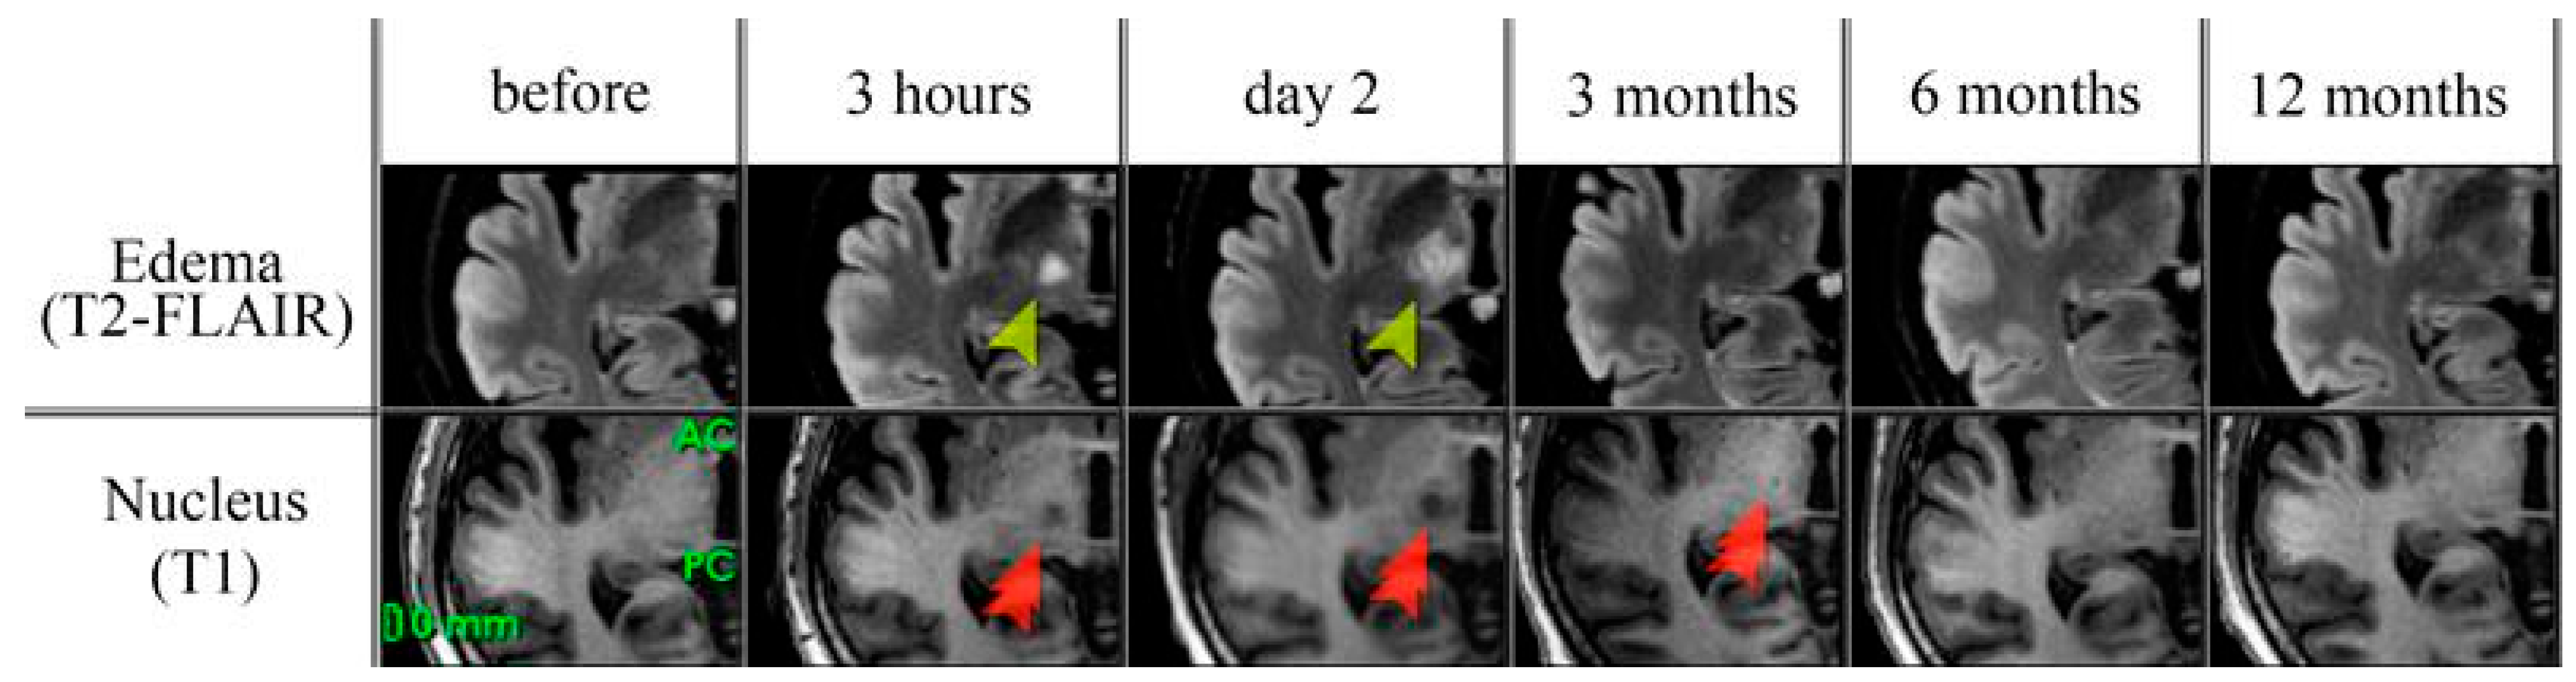

3.2.5. MRI Changes

| Before MRgFUS | 3 hrs Post-MRgFUS | Day 2 Post-MRgFUS | 3 Months Post-MRgFUS | 6 Months Post-MRgFUS | 12 Months Post-MRgFUS |

|---|---|---|---|---|---|

| NUCLEUS | |||||

| - | 194 [157; 238] | 394 [314; 504.5] | 29 [12; 52] | 9 [2; 20] | 9.5 [4; 24.75] |

| EDEMA | |||||

| - | 841 [709–1101] | 2718.5 [1974.5; 3426.25] | 37 [13.5–50.0] | 18 [0.5; 44] | 8 [0; 16] |

| FRACTIONAL ANISOTROPY | |||||

| 0.39 [0.36; 0.45] | 0.15 [0.13; 0.17] z = −4.014; p = 0.0001 * | 0.16 [0.14; 0.19] z = −3.823; p = 0.0001 * | 0.31 [0.25; 0.34] z = −2.897; p = 0.0038 * | 0.32 [0.26; 0.36] z = −1.334; p = 0.182 * | 0.32 [0.27; 0.57] z = −0.405; p = 0.687 * |